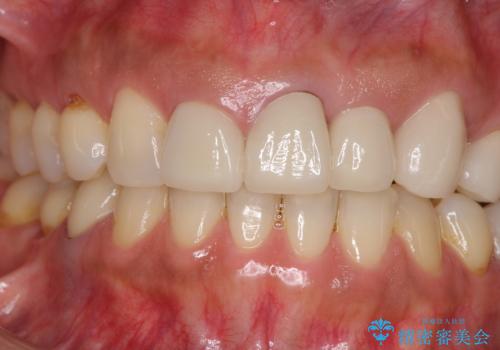

- 前歯の歯肉の高さが左右で異なっていることを気にして来院された患者様です。

歯肉レベルを調整するために歯周外科処置をおこない、その後にオールセラミッククラウンにて補綴することとしました。

歯肉の位置を整えるには歯周外科処置が必要であると説明した際には、なかなか踏み切ることができず、大変悩まれていました。

処置後の痛みはあまり気にならず、歯肉位置の左右差もほとんどなくなり、患者様には大変満足していただきました。